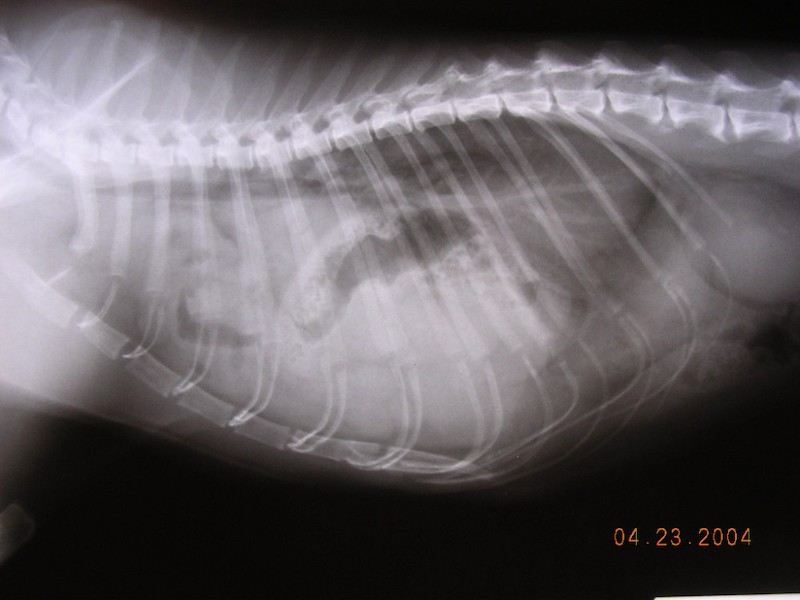

Diaphragmatic Hernias:

diaphragmatic hernia mcmichael sized

This is an internal tear in the diaphragm—the muscle separating the chest from the abdomen. Usually, this is caused by trauma, like a car accident, and it’s a critical emergency because organs can move into the chest and compress the lungs.